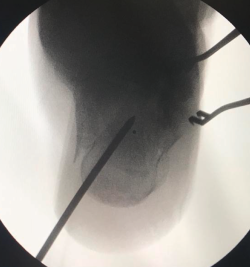

Figura 1. Abordaje del seno del tarso de 2-3 cm. Se realiza una línea que va desde el cuarto metatarsiano (4th) al peroné. F: fíbula.

Para realizar el abordaje del seno del tarso(13) se sigue una línea imaginaria que discurre desde el eje del cuarto metatarsiano hasta la punta del maléolo lateral, realizando una la incisión de 2-3 cm sobre esta línea (se puede ampliar la incisión tanto hacia proximal como a distal) (Figura 1). La disección se debe realizar con cuidado para no dañar el nervio sural ni a los tendones peroneos que cruzan la incisión (Figura 2). Finalmente, se debe abrir el ligamento peroneo-calcáneo para acceder a la articulación subastragalina posterior; este paso no ha demostrado provocar inestabilidad de tobillo durante la evolución posterior.